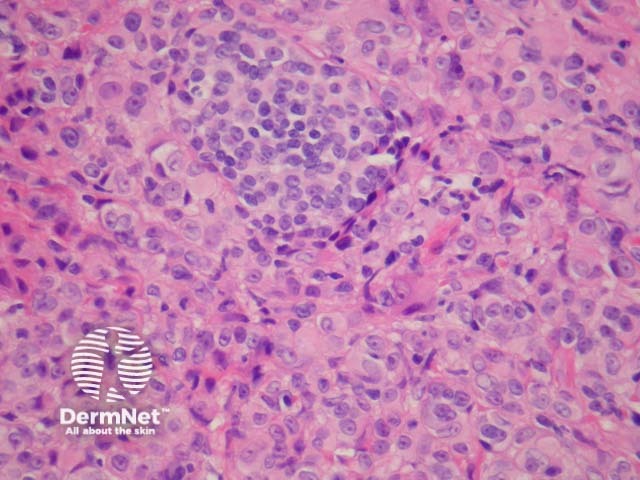

Cutaneous metastasis of melanoma can cause diagnostic confusion. The metastatic melanoma may invade the dermis or subcutis and form a nodular tumour mass without invasion of the overlying epidermis (figure 1). The pattern of growth may mimic a benign intradermal naevus at low power (figure 1) but at high power examination the nuclear atypia is usually obvious, there may be mitoses and there is minimal evidence of maturation (decrease in cell size) with descent in the dermis (figure 2). Usually the lack of epidermal involvement is a good clue the tumour is a metastasis from another site but sometimes the metastasis may invade the epidermis and closely simulate a primary melanoma.

Rarely, melanoma which has metastasised to the dermis may closely mimic a blue naevus (blue naevus-like melanoma, figures 3,4). This can cause considerable diagnostic difficulty and be impossible to correctly recognise without clinical information.